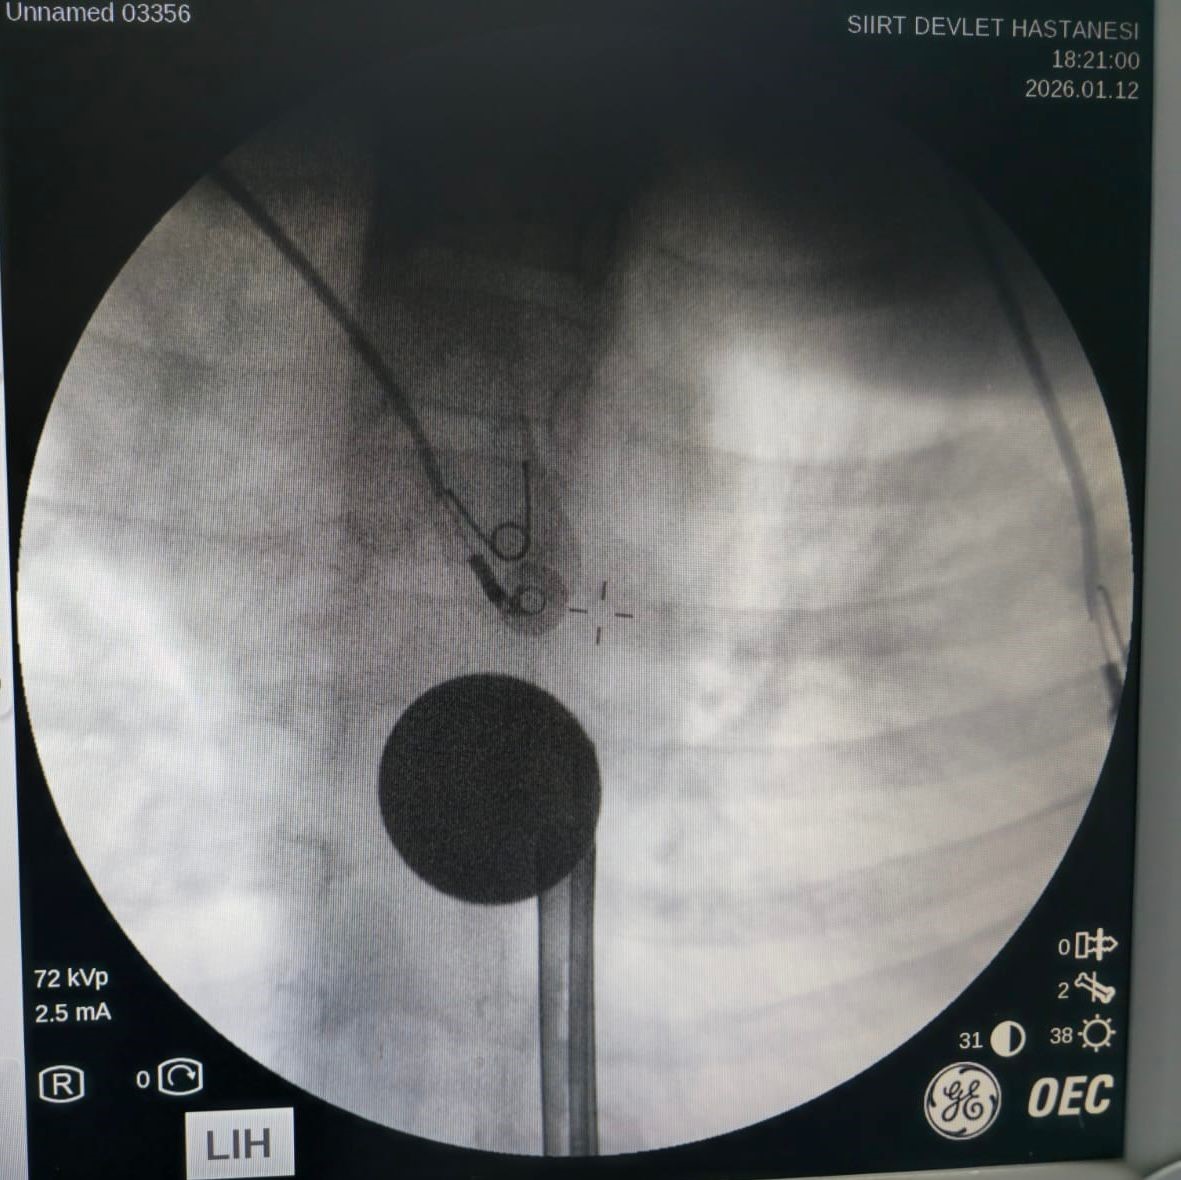

Yabancı cisim yutma şikayetiyle ailesi tarafından Siirt Eğitim ve Araştırma Hastanesine getirilen 8 yaşındaki Y.K., yapılan ilk değerlendirme ve görüntüleme tetkiklerinin ardından ilgili branşlarca operasyona alındı. Y.K.’nın yemek borusuna kadar ilerlediği tespit edilen madeni para, gastroenteroloji uzmanı Dr. Yaren Dirik ve kulak burun boğaz hekimi Yasin Gökçınar tarafından müdahale edilerek çıkartıldı. Operasyonun ardından bir süre gözlem altında tutulan Y.K., tedavisinin tamamlanmasıyla taburcu edildi.

Siirt Eğitim ve Araştırma Hastanesi Başhekim Yardımcısı Uzman Dr. Burak Özkan, çocuk hastalarda yabancı cisim yutma vakalarının ciddi riskler oluşturabileceğini söyledi. Uzm. Dr. Özkan, “Hastanemize başvuran 8 yaşındaki hastamızın yemek borusuna kaçan madeni para, gastroenteroloji ve KBB ekiplerimizin koordineli ve titiz çalışmasıyla herhangi bir komplikasyona yol açmadan başarılı bir şekilde çıkarılmıştır. Operasyon süreci sorunsuz geçmiş olup hastamızın genel durumu iyidir” dedi.